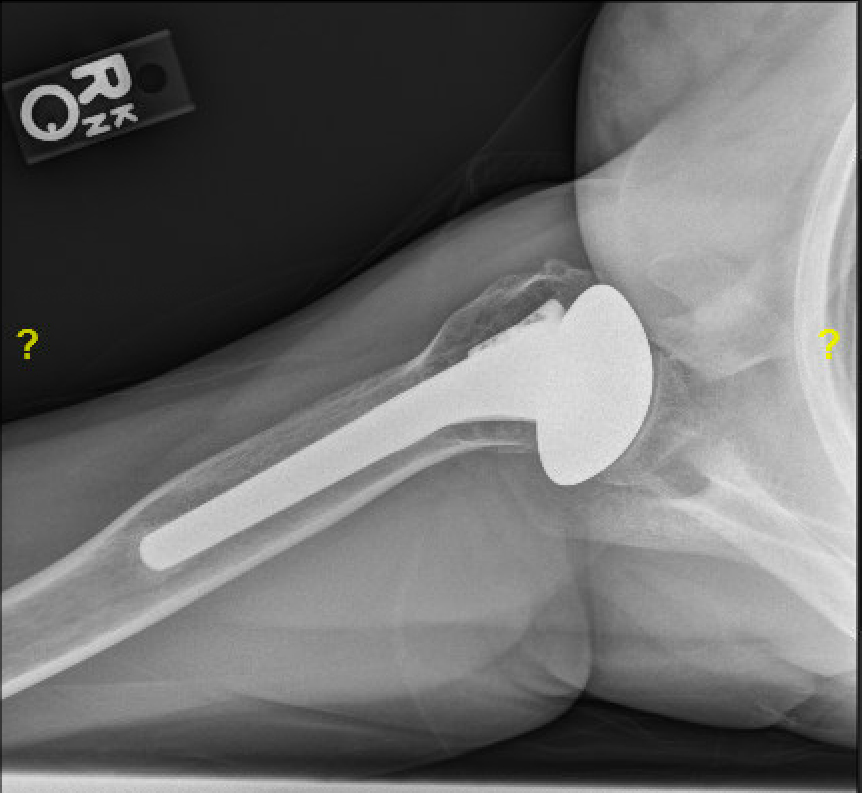

Her postoperative films are shown below. Note the smooth standard length humeral stem was secured using impaction auto grafting with bone harvested from the humeral head resulting in a low filling ratio.

At six years after surgery she reported, "I am doing well! I am completely pain free and able to do everything I want to do with no limits. I actually forget that I have a metal shoulder most of the time" Her x-rays six years after surgery are shown below. Note the stability of the impaction grafted humeral component, the absence of glenoid erosion, and the remodeling of the glenoid surface.

She sent these images of her 9 year old ream and run. Note the remodeling of her glenoid joint surface and the secure fixation of the impaction grafted smooth humeral stem without evidence of stress shielding.